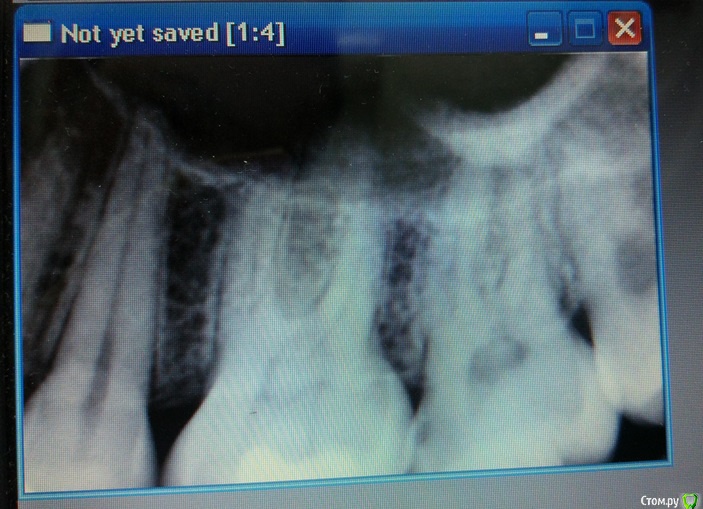

Malalejandra Опубликовано 1 февраля, 2017 Автор Поделиться Опубликовано 1 февраля, 2017 Еще один снимок, прицельный, сделан сегодня. Ссылка на комментарий

red_butler Опубликовано 1 февраля, 2017 Поделиться Опубликовано 1 февраля, 2017 похоже что на седьмом кариес, лечите Ссылка на комментарий

shishok Опубликовано 1 февраля, 2017 Поделиться Опубликовано 1 февраля, 2017 Я бы еще проверила нижние 6 и 8(6-лечить,8-проще удалить).На верхнем 7 кариес(как уже раньше сказали). Ссылка на комментарий